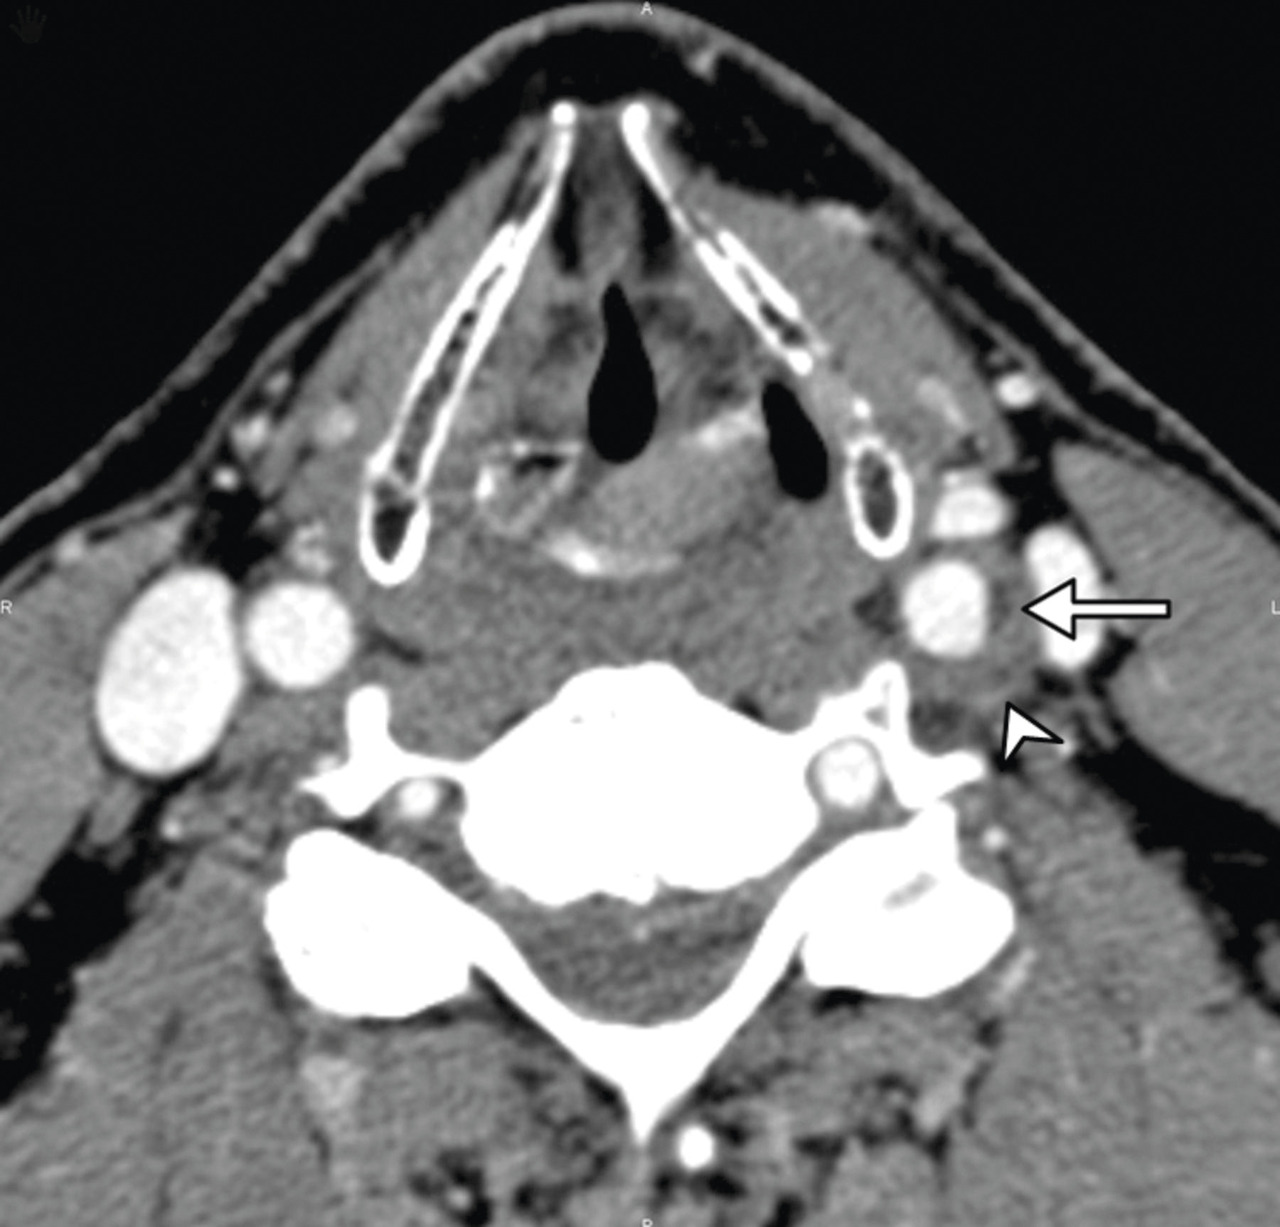

Une IRM cérébrale et cervicale avec injection est réalisée. Elle met en évidence, à l’étage cervical, un épaississement excentré marqué, en isosignal T1 et hétérogène en T2. Une prise de contraste périphérique de la bifurcation carotidienne gauche est également constatée. L’ensemble est évocateur d’un TIPIC syndrome (fig. 2 ).

Une IRM cérébrale et cervicale avec injection est réalisée. Elle met en évidence, à l’étage cervical, un épaississement excentré marqué, en isosignal T1 et hétérogène en T2. Une prise de contraste périphérique de la bifurcation carotidienne gauche est également constatée. L’ensemble est évocateur d’un TIPIC syndrome (

Le diagnostic se fait par imagerie (échodoppler des TSA, IRM cervicale). L’infiltration périvasculaire en regard de la bifurcation carotidienne est un signe pathognomonique. S’y associe parfois une discrète réduction du calibre vasculaire.